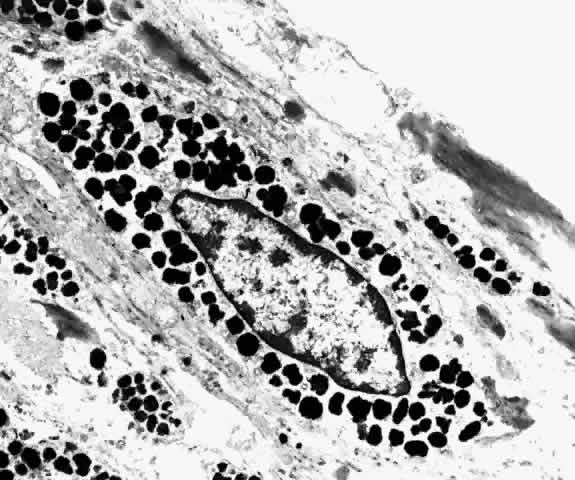

as much as 70% of the cytoplasm may be occupied by melanosomes (Figs. 29 and 30).22  Fig. 29. Choroidal melanocytes (mel) intermixed with fibrocytes (f). Spindle-shaped melanocytes have elongated nuclei (s), polyhedral melanocytes have oval nuclei (p), and both types of melanocytes have prominent intracytoplasmic melanin

pigment granules. (× 4750) Fig. 29. Choroidal melanocytes (mel) intermixed with fibrocytes (f). Spindle-shaped melanocytes have elongated nuclei (s), polyhedral melanocytes have oval nuclei (p), and both types of melanocytes have prominent intracytoplasmic melanin

pigment granules. (× 4750)